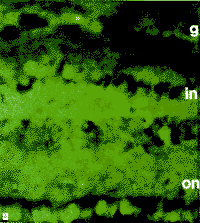

用正常眼压性青光眼患者的视神经乳头和视网膜抗人IgG和IgA抗体进行免疫染色。表明这些组织中有血清免疫球蛋白。神经节细胞和视网膜内外核层的免疫染色明显。对照抗体不使这些组织染色,对照眼用这些抗体均无染色(图7)。

图7 有人免疫球蛋白荧光结合单克隆抗体的正常眼压性青光眼患者的视网膜免疫染色。患者视网膜切片的节细胞(g)和外(on)及内核层(in)可见有抗人IgA(A)或IgG(C)抗体的免疫染色。在年龄相匹配的有抗人IgA(B)或IgG(D)抗体对照眼中除正常的自体荧光外未见免疫染色